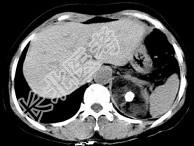

- 单项选择题男性,28岁, 左腰背酸胀5个月,CT检查如图所示, 应诊断为 ( )

A、左肾上腺髓样脂肪瘤

B、左肾上腺错构瘤

C、左肾上腺嗜铬细胞瘤

D、左肾上腺腺瘤

E、左肾上腺转移瘤